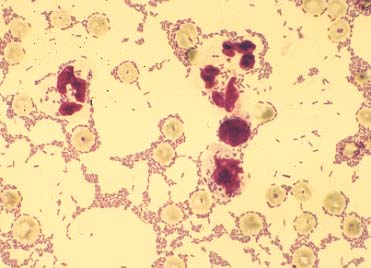

Liquor eines Kalbes mit bakteriell bedingter Meningoenzephalitis (May-Grünwald-Färbung): Vermehrung segmentkerniger Leukozyten und massenweise Stäbchen (E. coli).